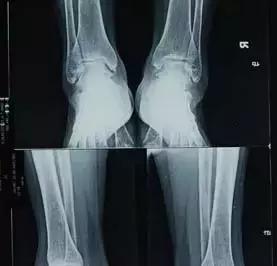

一般的骨、关节结核的好发部位首先为脊椎,其次为髋关节及膝关节、短骨及长骨骨干。外伤可使隐性骨结核病灶变成活动性骨结核。负重大或运动多的肢体或关节发生率较高,以负荷最重的胸腰段最易发生结核病。下肢结核比上肢结核多见。